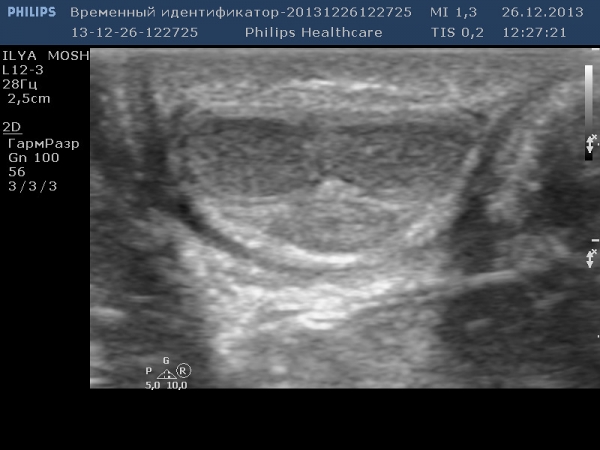

загадка в паху